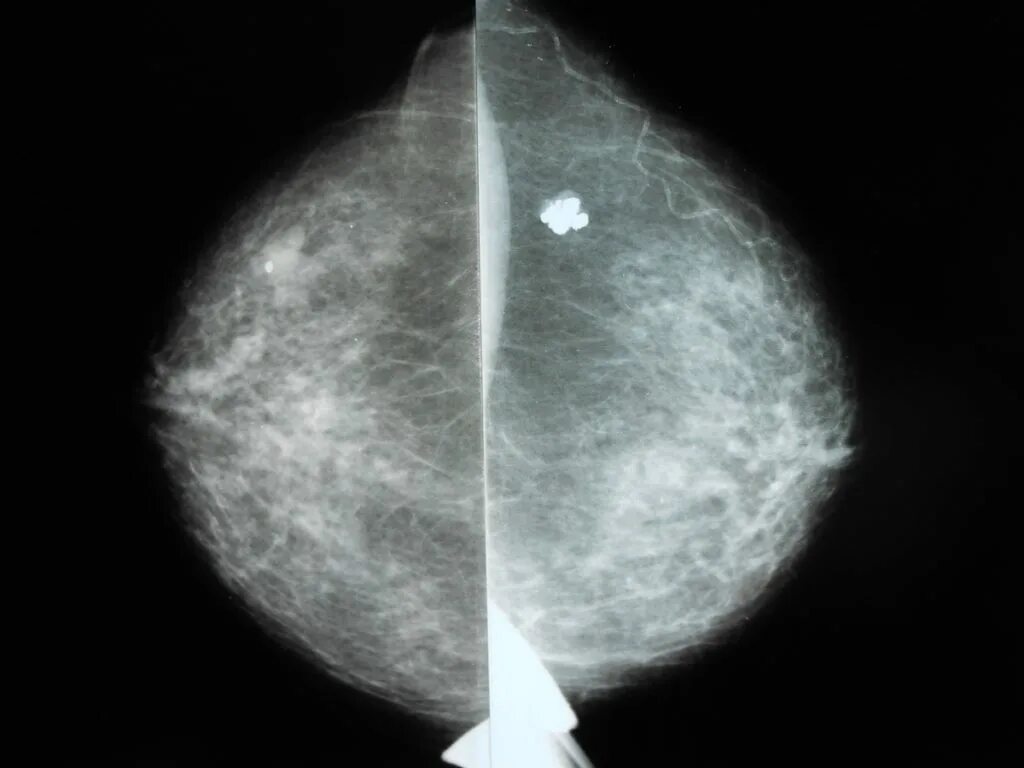

Микрокальцинаты в молочной железе что это